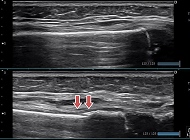

肉離れ

(腓腹筋)

診断だけでなく、治癒過程も評価できます。